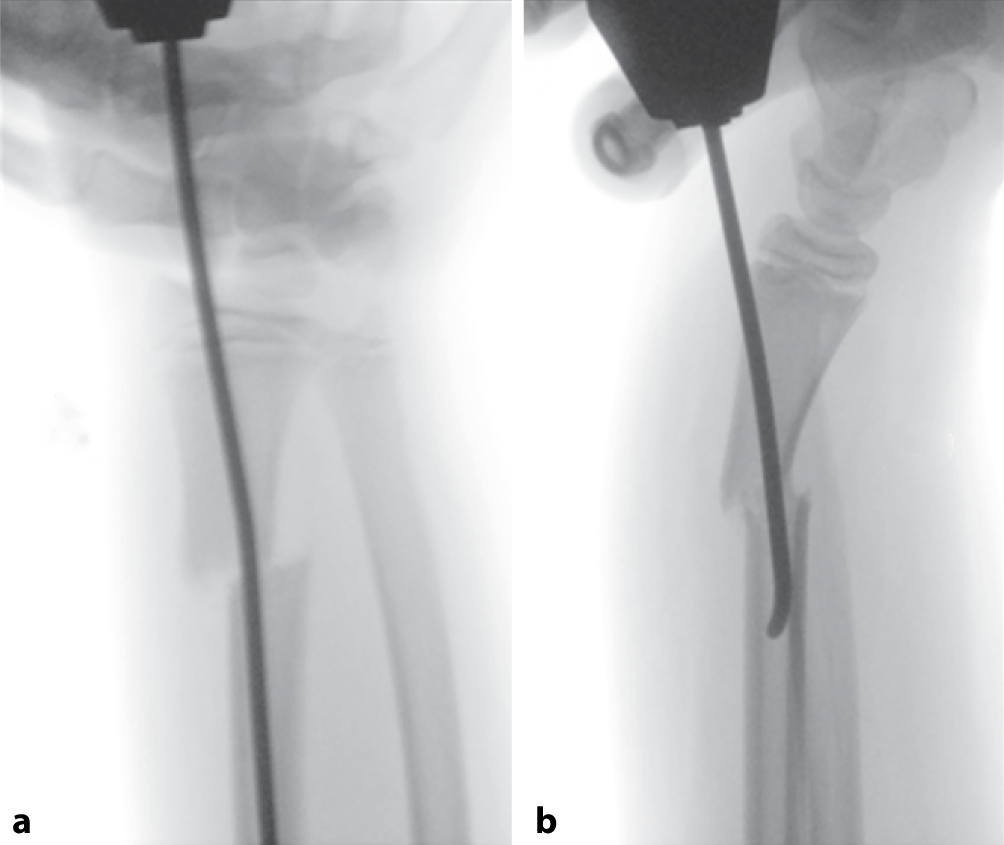

Abb. 6

Intraoperative Bilder. a Radiologische Darstellung des Eingehens mit dem Pfriem im 45°-Winkel, da der Schaft hier einen kleinen Durchmesser hat, ist noch mehr darauf zu achten, nicht die Gegenkortikalis zu perforieren. b Vorschieben des TEN bis zur Fraktur unter drehenden Bewegungen, dann Reposition der Fraktur. Hier kann das in der Abb. 7 beschriebene Kapandji-Manöver hilfreich sein, um eine offene Reposition zu vermeiden. Ebenfalls sollte die Kufe des TEN mit der Flachzange begradigt werden. c Bei reponierter Fraktur Vorschieben des TEN bis knapp unter die Wachstumsfuge. de Additive antegrade Versorgung der Ulna und Ausrichten der TEN-Enden bis zur optimalen Frakturstellung